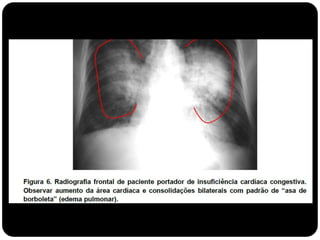

 O padrão alveolar ou do espaço aéreo é caracterizado por

opacidade homogênea.

 Ocorre pela ocupação do espaço aéreo por outras

substâncias que não o ar: exsudato nas pneumopatias,

transudato nos edemas pulmonares, sangue, células

neoplásicas e materiais estranhos no caso de aspiração (ex.

aspiração de óleo mineral)

Padrão Alveolar

 Forma repentina (horas a dias): hemorragia pulmonar

(trauma, vasculites), pneumonia (febre e tosse produtiva),

edema pulmonar (cardiogênico e não cardiogênico);